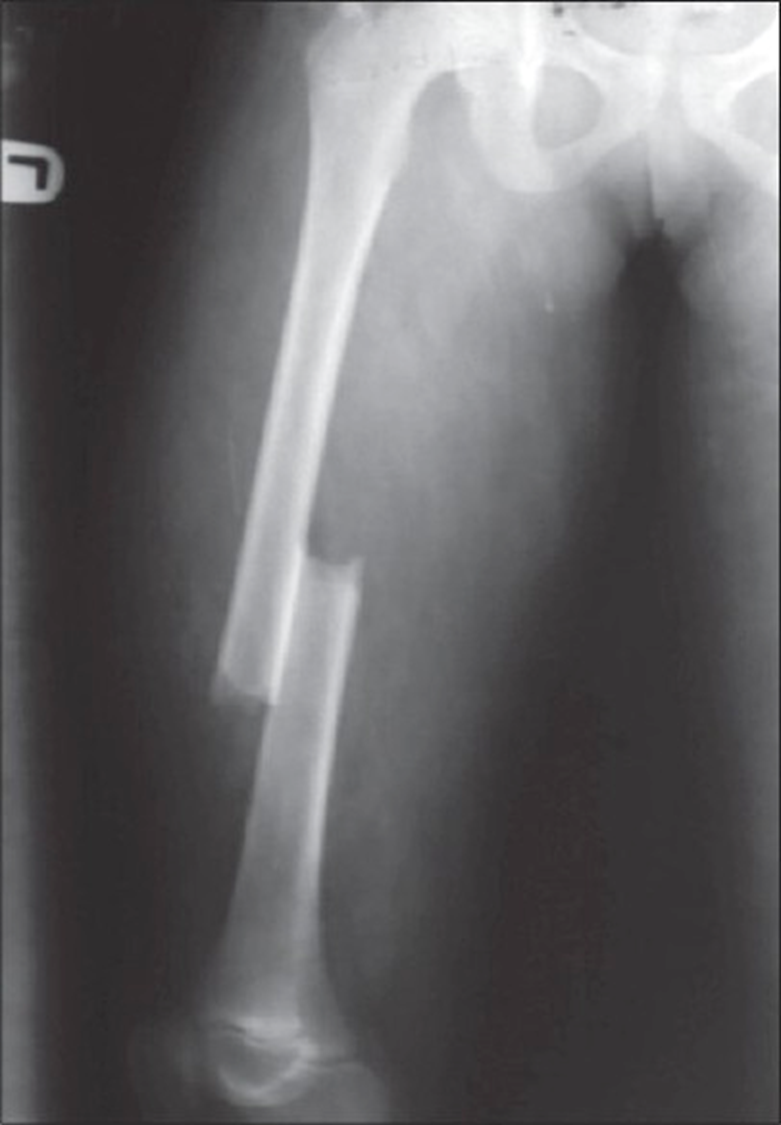

describe this fx using anatomic site and extent

junction of the middle and distal third